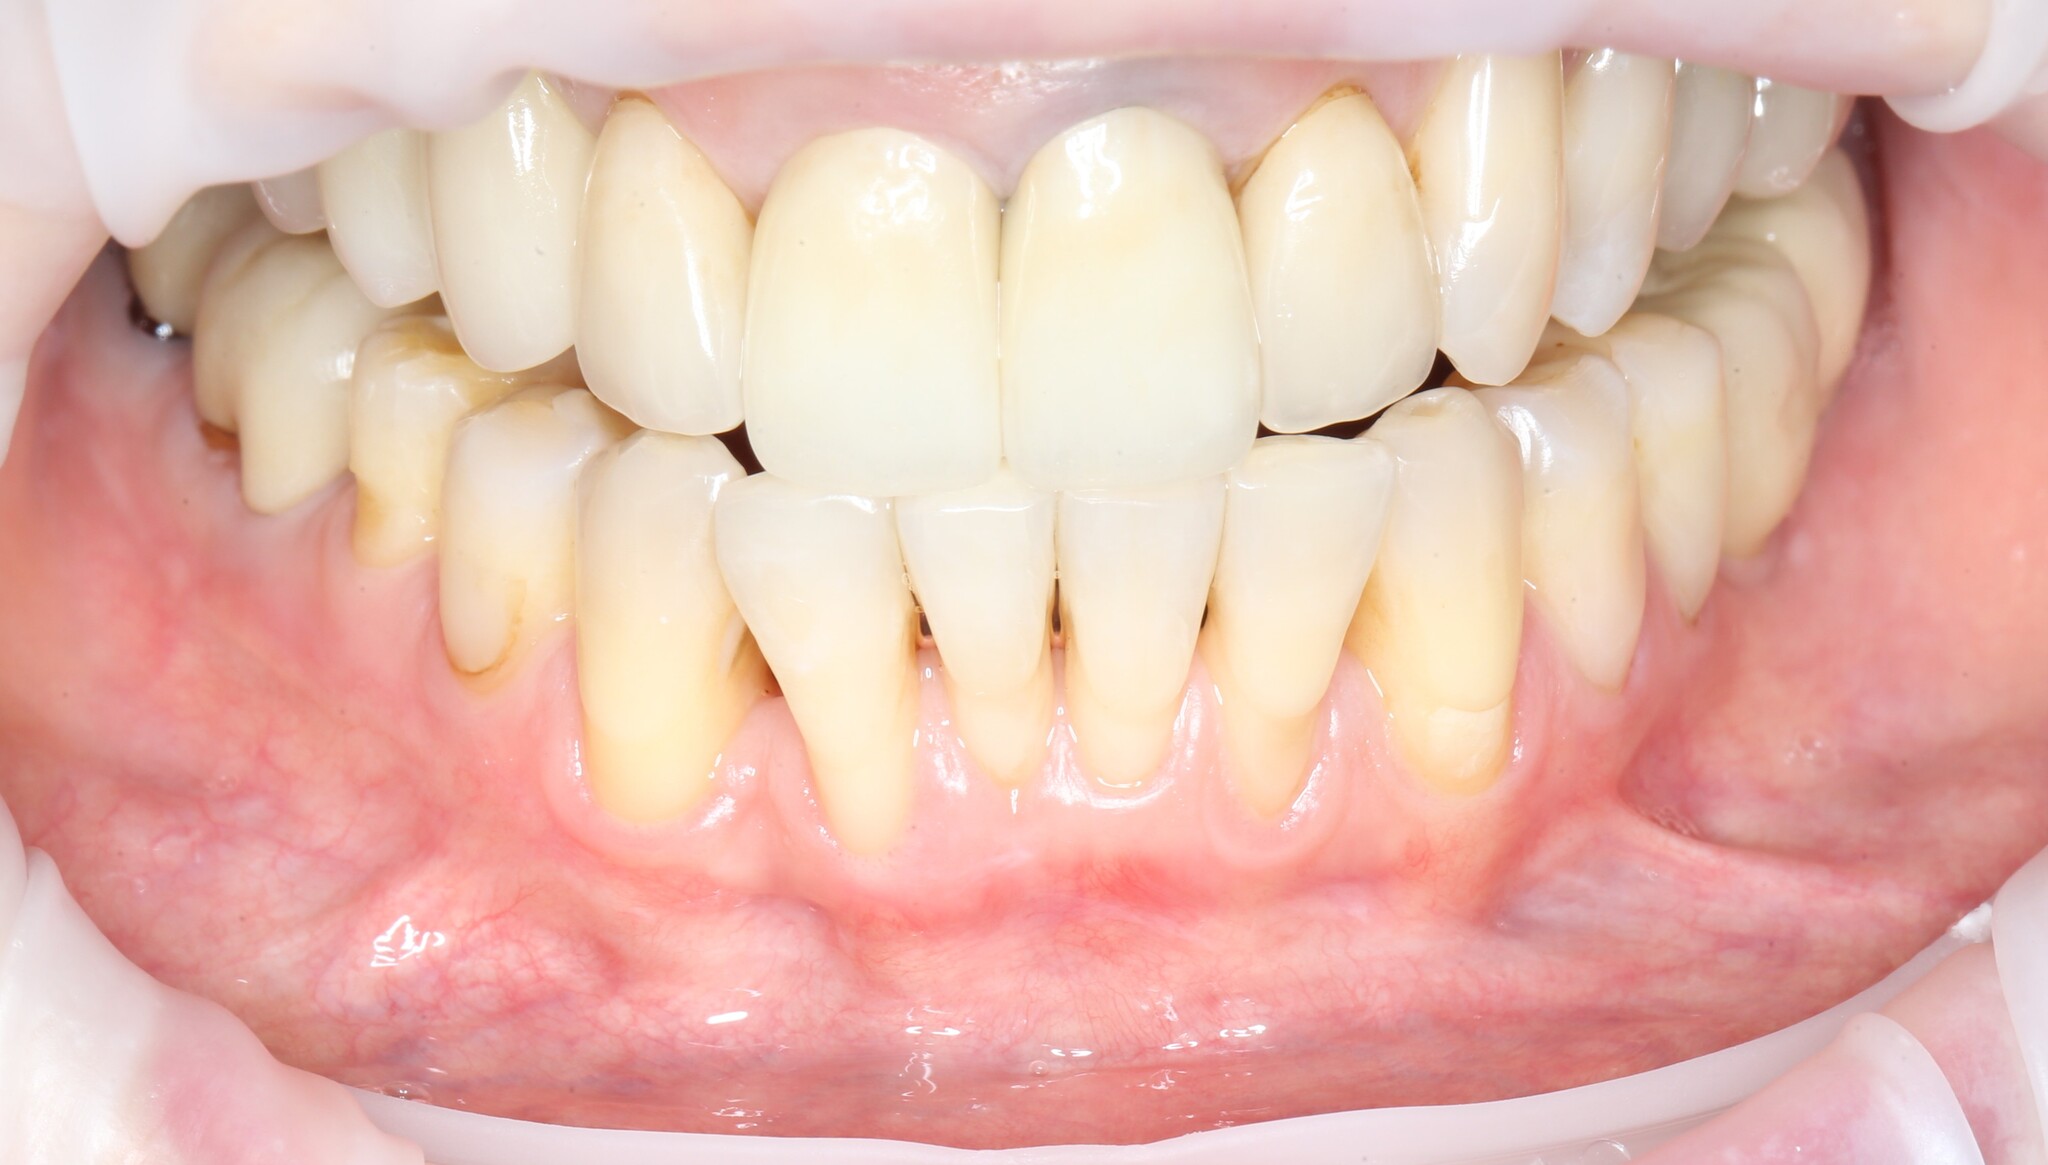

После снятия швов через несколько месяцев область операции выглядит так:

Рубец будет потихоньку разглаживаться.

Сравним:

Вот так и выглядит операция – вестибулопластика.